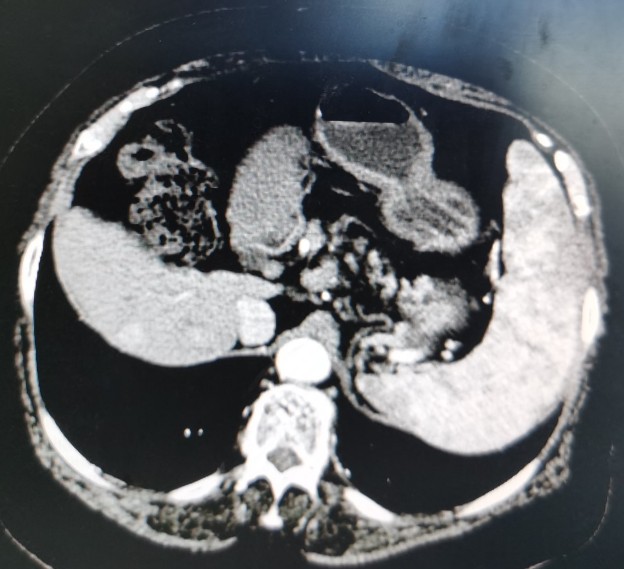

栓塞后复查的CT

栓塞后CT

肿瘤栓塞良好